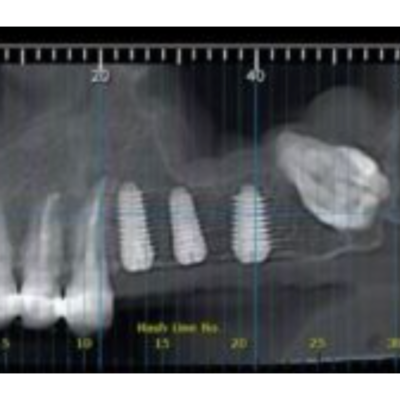

Hey, guys! Dragos from Romania here! I’ve made a bit of courage to start posting and asking about some of my cases (since i started doing them more frequently). Please don’t judge mistakes since I don’ t pretend to be a guru of surgery of some sort. Actually I still consider myself a begginer in that matter. Anyway, here’s a case I did this month. I decided to place 3 implants on the left and I will follow with 3 on the right. Patient did not want all at once. She is a light smoker, no general pathology except a history of clostridium difficilae from antibiotics(she surpassed it 8 years ago). Surgery went fine, I know i could have placed 2.4 more palatally and 2.5 with a bit more vestibular inclination, but I did it freehand and as I said, I am still learning. I decided to keep the wisdom tooth there since it did not bother her at all and I had to do a bit of troughing to extract it. Second cbct is 5 days post surgery. She accused a sensation of fullness in the sinus and a bit of pressure. As you can see, there is a sinus reaction. She was on augmentin antibiotics after surgery and I also gave her some sinus meds(for drainage). 3 weeks later she is fine, no more symptoms. Question is: why did she develop so quickly this sinusitis. Could’ve been because of a possible bacterial colonization tru the wisdom tooth parh after i did the flap? (Yes i did go a bit distal with the incision, but no vertical releasing ones where necessary). I will prolly post another x ray to see if there is cronicization. The time between first and 2nd cbct is about 5 weeks.

• Yes! I did the ct to see if there is a trouble with an implant. I was scared of maybe going to deep in the sinus, bur apparently that was not the case. I

• Hey Dragos! Nice to hear from you. Very interesting case period. Looking at some of your updates, and everything has cleared and improved. It looks like potentially the one implant that was the closest to the sinus. You may have drilled slightly deeper in one area that potentially enter the sinus, which allowed a little bit more fluid to enter the sinus cavity, causing a little bit of irritation. But it looks like that was short-lived and everything is better now. Thanks so much for sharing.